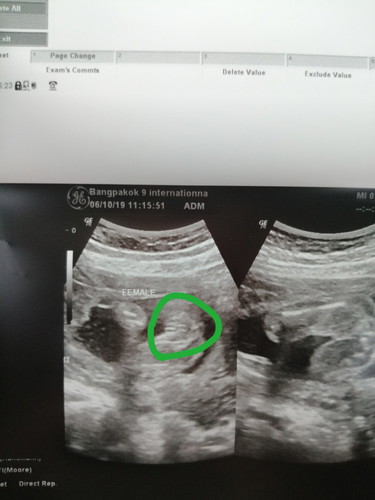

5เดือนครึ่งผลซาวด์ได้ลูกสาวค่ะ

แม่ๆบ้านใหนรู้เพศลูกบ้างค่ะแสดงตัวหน่อยค่ะพอดีบ้านนี้อยากได้ลูกสาวก็สมใจปราถนาพ่อเขามากเลยค่ะ